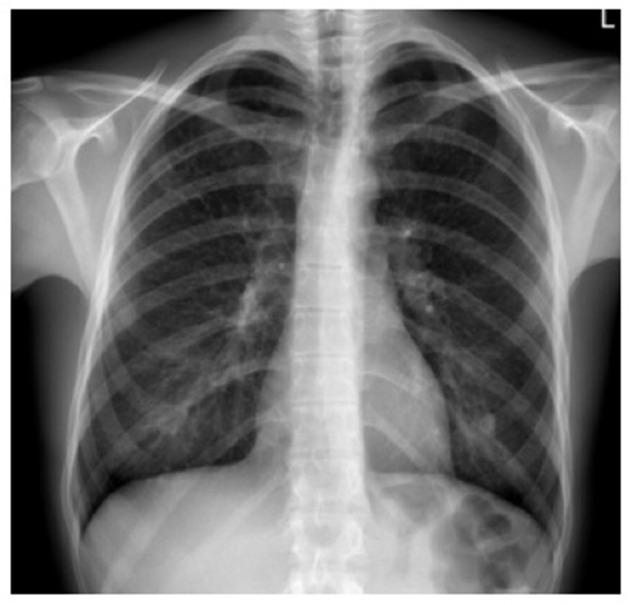

Pulmonary Langerhans cell (LC) histiocytosis (PLCH) has unknown cause and is a rare neoplastic disorder characterized by the infiltration of lungs and various organs by bone marrow-derived Langerhans cells with an accompanying strong inflammatory response. These cells carry somatic mutations of gene and/or , and genes, which cause activation of the mitogen-activated protein kinase (MAPK)/extracellular signal-regulated kinase (ERK) signaling pathway. PLCH occurs predominantly in young smokers, without gender predominance. Lungs might be involved as an isolated organ or as part of a multiorgan disease. High-resolution computed chest tomography plays an outstanding role in PLCH diagnosis. The typical radiological picture of PLCH is the presence of small intralobular nodules, "tree in bud" opacities, cavitated nodules, and thin- and thick-walled cysts, frequently confluent. Histological examination of the lesion and demonstration of characteristic eosinophilic granulomas with the presence of LCs that display antigen CD1a or CD207 in immunohistochemistry are required for definite diagnosis. Smoking cessation is the most important recommendation for PLCH patients, but treatment of progressive PLCH and multisystem disease is based on chemotherapy. Recently, new targeted therapies have been implemented.

肺朗格汉斯细胞(LC)组织细胞增多症(PLCH)病因不明,是一种罕见的肿瘤性疾病,其特征是骨髓来源的朗格汉斯细胞浸润肺和各种器官,并伴有强烈的炎症反应。这些细胞携带基因和/或基因以及基因的体细胞突变,导致丝裂原活化蛋白激酶(MAPK)/细胞外信号调节激酶(ERK)信号通路激活。PLCH主要发生在年轻吸烟者中,无性别差异。肺部可能作为孤立器官受累,也可能是多器官疾病的一部分。高分辨率胸部计算机断层扫描在PLCH诊断中起着重要作用。PLCH典型的放射学表现为小叶内小结节、“树芽”状阴影、空洞性结节以及薄壁和厚壁囊肿,常相互融合。明确诊断需要对病变进行组织学检查,并在免疫组织化学中显示具有表达抗原CD1a或CD207的LC的特征性嗜酸性肉芽肿。对PLCH患者最重要的建议是戒烟,但对于进行性PLCH和多系统疾病的治疗基于化疗。最近,已实施了新的靶向治疗。